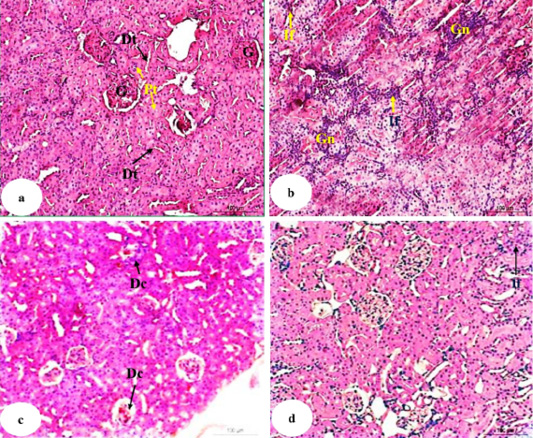

Photomicrographs of HandE stained kidney sections of normal (a), doxorubicin-administered group (b) and doxorubicin-administered groups treated with U. fasciata (c) and AgNPs/U. fasciata (d). G: glomeruli; Pt: proximal tubule; Dt: distal tubule; Gn: glomerulonephrosis; If: inflammatory cells infiltration; Dc: degenerative changes in glomeruli (with hypocellularity) and in tubules.